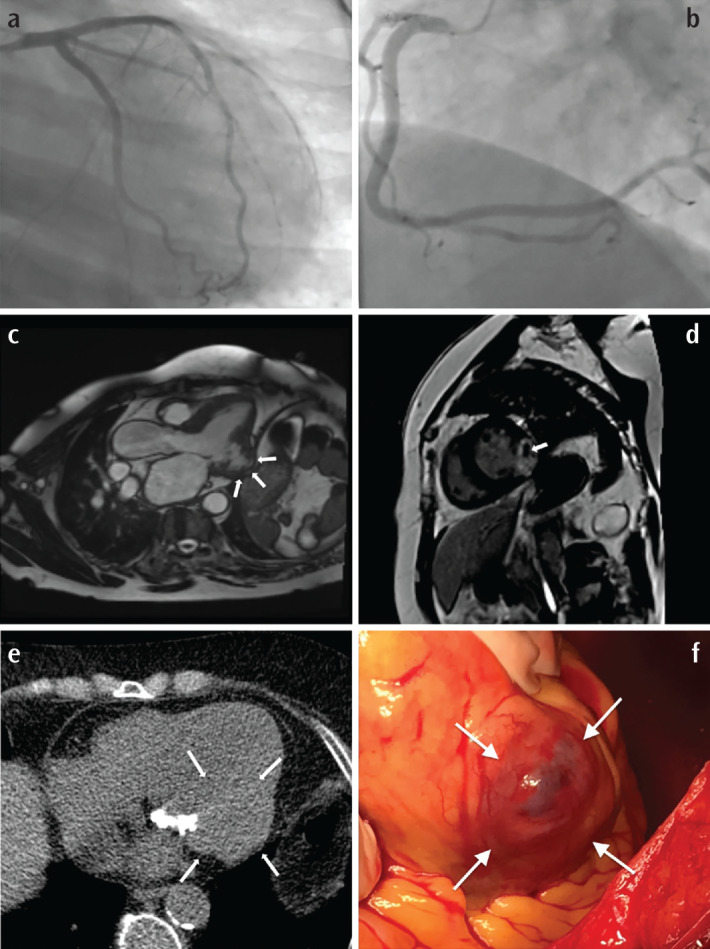

Is MINOCA Syndrome Causing Fatal Left Ventricular Aneurysms Less Innocent than It Appears?